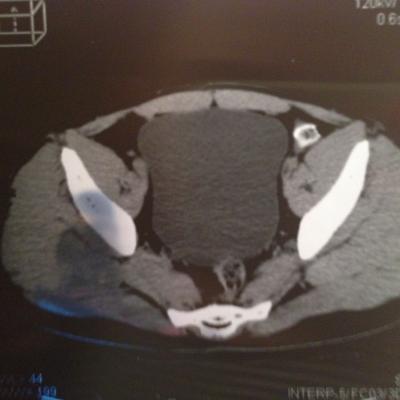

проведена МСКТ области таза!Внеорганных дополнительных патологических образований,лимфаденопатии или свободной жидкости в области таза не выявлено.

Мочевой пузырь-наполнен,стенки не утолщенны,паравезикально-без грубой органки.

Граница между предстательной железой и пузырем несколько четкая,контур пузыря на данном уровне не деформирован.

Предстательная железа-без грубой органики,еденичные микрокальцинаты.

Семенные пузырьки-конфигурация не совсем типична,примерный размер правого 26*28мм.Отмечаются признаки кистовидной трансформации и микрокальцинации обоих пузырьков.Наибольшая из кист слева достигает 9 мм.Обращает на себя внимание неравномерная кальцинация стенок крупных регионарных(текстикулярных)артерий с обоих сторон.

Костно-деструктивных изменений характерных для mts со стороны костей таза не отмечено.

Параректальная клетчатка-не изменена,патологически увеличенных лимфоузлов в параректальном пространстве не отмечено.M.m.levator ani-без особенностей.

Заключение:на момент исследования,КТ-данных за наличие внеорганных дополнительных патологических образований,лимфоденопатии или свободной жидкости в области таза не выявлено.КТ-признаки в пользу проявлений калькулезного везикулита с элементами кистовидной трансформации семенных пузырьков.